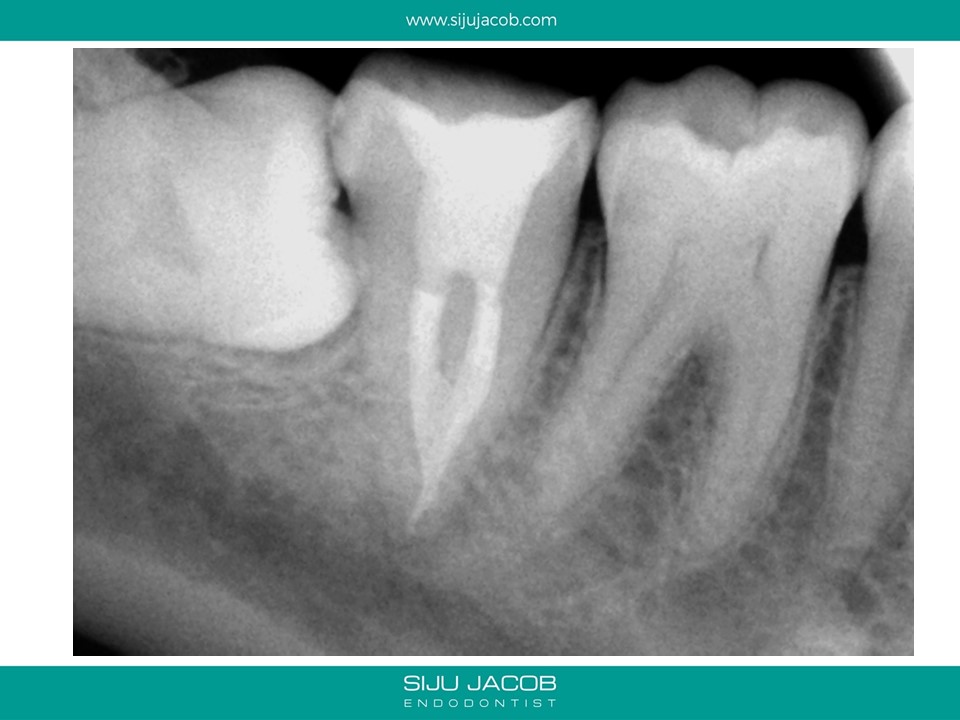

Written by Siju JacobApril 12, 2020 Mandibular second molar: 3-2-1 combo This Mandibular second molar started off as 3 canals merging into 2 and finally exiting as a single portal of exit. Share this: Share on X (Opens in new window) X Share on Facebook (Opens in new window) Facebook Like Loading... Related Leave a comment Cancel reply Δ